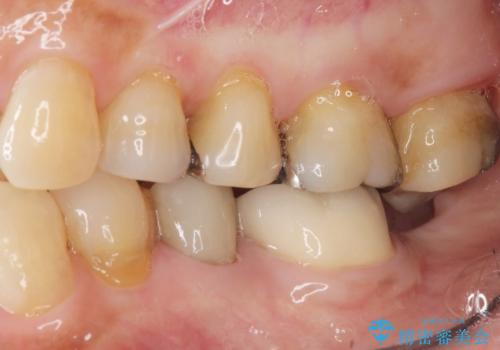

- 歯並びと滑舌が気になるとご相談にいらした方です。矯正治療に先立って、舌小帯切除を行いました。

舌小帯は、舌の下にある線維性のスジです。これが極端に短かったり、強直していると、舌の運動や発音に弊害をきたすことがあります。